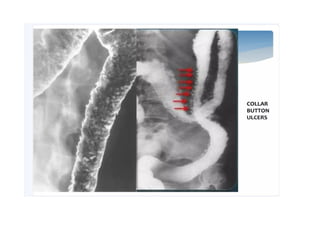

• aphthous ulcers seenin the active phase of disease as punctate collection of barium with surrounding radiolucent halo due to mucosal edema

• When thedisease progresses, the ulcers coalesce and form deep linear ulceration separating out the edematous mucosa. This is seen on barium studies as cobble stoning.